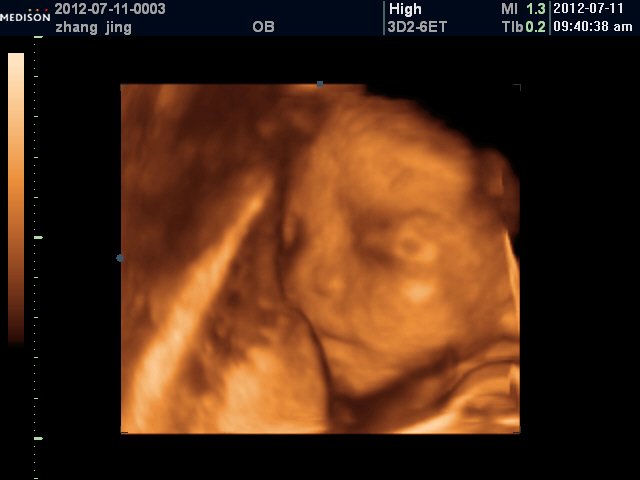

患者信息:女 28岁 陕西 西安 病情描述(发病时间、主要症状等):具体的:左侧脑室后角1.2cm, 右侧未探及, 羊水最大深度7.8cm,羊水指数24.4cm,双顶径6.9cm,下肢可显示,脊柱连续想得到怎样的帮助:是不是胎儿有问题啊?说什么可能脑积水,脊柱裂,……记不得了,让过个月去再查4维。有没有什么更好的办法赶紧检查出来呢?曾经治疗情况及是否有过敏、遗传病史:无遗传史,有点贫血